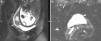

Renal colic is a common reason for presentation to emergency departments, and imaging has become fundamental for the diagnosis and clinical management of this condition. Ultrasonography and particularly noncontrast computed tomography have good diagnostic performance in diagnosing renal colic. Radiologic management will depend on the tools available at the center and on the characteristics of the patient. It is essential to use computed tomography techniques that minimize radiation and to use alternatives like ultrasonography in pregnant patients and children. In this article, we review the epidemiology, clinical and radiologic presentations, and clinical management of ureteral lithiasis.